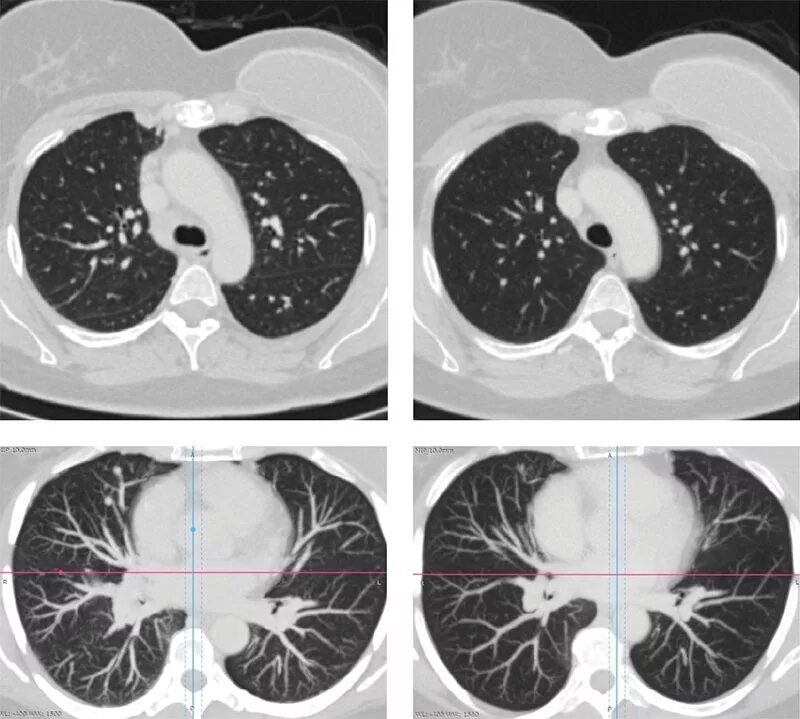

Рмж метастазы в легкие